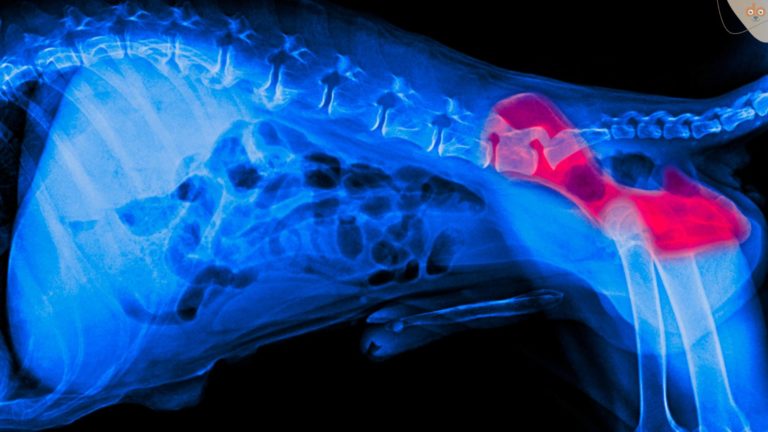

Die entscheidende Methode zur Diagnose von Hüftdysplasie ist jedoch die Bildgebung, insbesondere Röntgenaufnahmen. Diese Bilder geben Aufschluss über den Grad der Fehlstellung, das Ausmaß der Arthrose und andere strukturelle Veränderungen im Hüftgelenk. Für eine genaue Diagnose und Einstufung der Schwere der Dysplasie werden diese Röntgenbilder oft nach spezifischen Kriterien ausgewertet, die von Tierorthopäden oder spezialisierten Diagnosezentren festgelegt werden. In einigen Fällen kann es notwendig sein, weiterführende bildgebende Verfahren wie Computertomographie (CT) oder Magnetresonanztomographie (MRT) einzusetzen, um detailliertere Informationen über den Zustand der Hüftgelenke und das umgebende Gewebe zu erhalten.